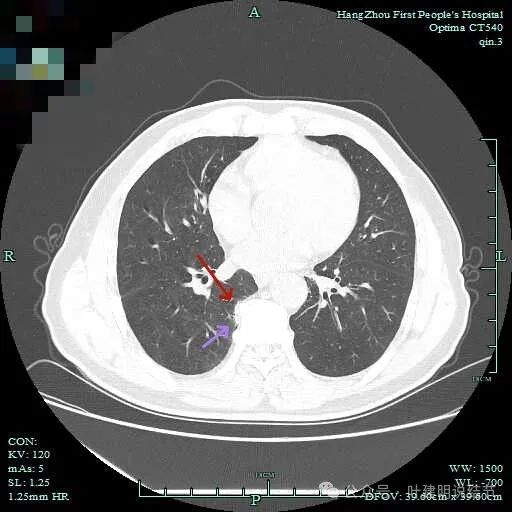

病仍明显,从上到下,觉得应该是成片的。

表面不平毛刺,实性密度为主。

微小血管有,但无异常增粗。

病灶实性,边缘不光滑。

实性密度,片状,条状。

病灶实性,缺乏膨胀性。

上图呈结节状,表面不平,有少许磨玻璃成分。

结节状,密度高,边缘欠光滑。

与脊柱之间有间隙,表面有细毛刺。

表面不平,似有细支气管截断征。

边缘不平毛糙。